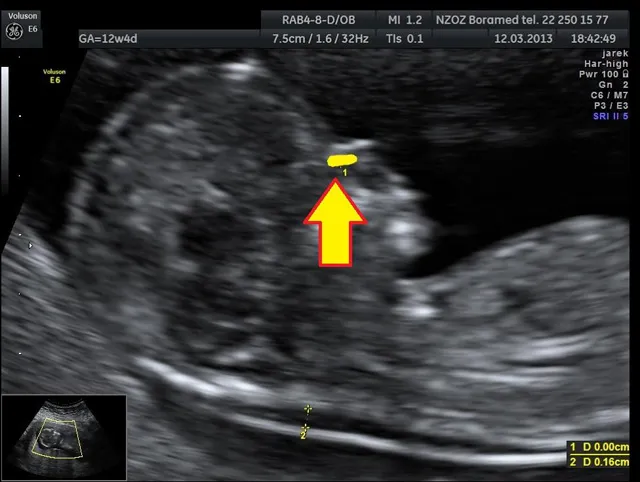

USG genetyczne I trymestru (11-14 tydzień): co lekarz widzi na monitorze?

USG genetyczne, wykonywane między 11. a 14. tygodniem ciąży, jest jednym z kluczowych badań przesiewowych. Pozwala ono na ocenę anatomii płodu oraz identyfikację tzw. markerów wad genetycznych. Lekarz uważnie przygląda się między innymi przezierności karkowej (NT), obecności kości nosowej (NB), a także ocenia przepływy w przewodzie żylnym i czynność zastawki trójdzielnej. Nieprawidłowe wartości tych parametrów mogą sugerować zwiększone ryzyko wystąpienia najczęstszych trisomii, takich jak zespół Downa (trisomia 21), zespół Edwardsa (trisomia 18) czy zespół Patau (trisomia 13).